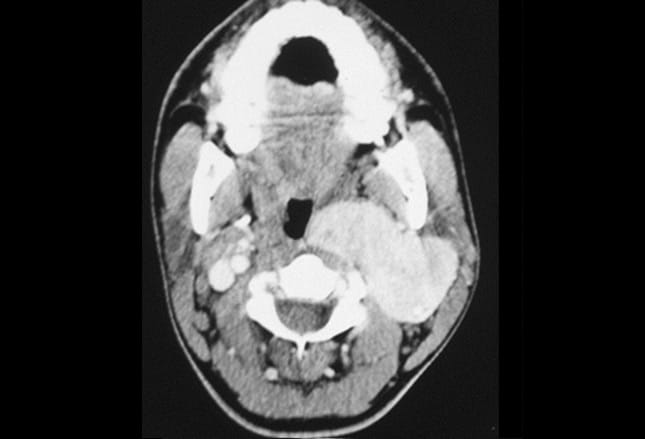

Universitätsklinikum heidelberg bösartige tumoren des. Bösartige erkrankungen des kopfhalsbereiches. Bösartige tumoren des mundrachens (oropharynx) in 80% der fälle handelt es sich bei den bösartigen tumoren desmundrachens um plattenepithelkarzinome. Ausgangsorgan für die meistenplattenepithelkarzinome sind die mandeln und der zungengrund.Wicht. Síntomas del cáncer de boca, tratamientos y esperanza de. Síntomas del cáncer de boca. Un cáncer en la boca puede aparecer como una placa blanca (leucoplasia), tipo llaga o como una úlcera en la boca (labios, lengua o cavidad oral).Al principio la lesión puede ser indolora pero con el tiempo, cuando tumor está avanzado, producir una sensación de ardor o dolor continuo. Diccionario de cáncer national cancer institute. El diccionario de cáncer del nci contiene 8,390 términos relacionados con el cáncer y la medicina.. Ofrecemos un widget que usted puede añadir a su sitio web para que sus usuarios puedan buscar términos de cáncer. C01 zungenwurzelkarzinom averbis. Sämtliche inhalte der icd10gm suche basieren auf den klassifikationen und kodierungen icd 10 gm 2017 von dimdi deutsches institut für medizinische dokumentation und information. Zungenkarzinom doccheck flexikon. Bei einem karzinom im bereich des zungenrandes und des zungenrückens erfolgt eine großzügige exzision, entweder als zungenteilresektion oder als glossektomie. Sind die nachbarstrukturen infiltriert, kann eine enblocresektion mit den angrenzenden weichteilen und teilen des unterkiefers nowendig werden. Full text of "lehrbuch der lokalanästhesie, für studierende. Search the history of over 347 billion web pages on the internet. Cáncer de cabeza y cuello artículos intramed. Consejos para no especialistas • derive al especialista con urgencia a todos los pacientes con ronquera, estridor, problemas para tragar, dolor de oído unilateral, nudo en el parche de cuello, úlceras de color rojo o blanco en la boca, parálisis de pares craneales, o masas orbitales.